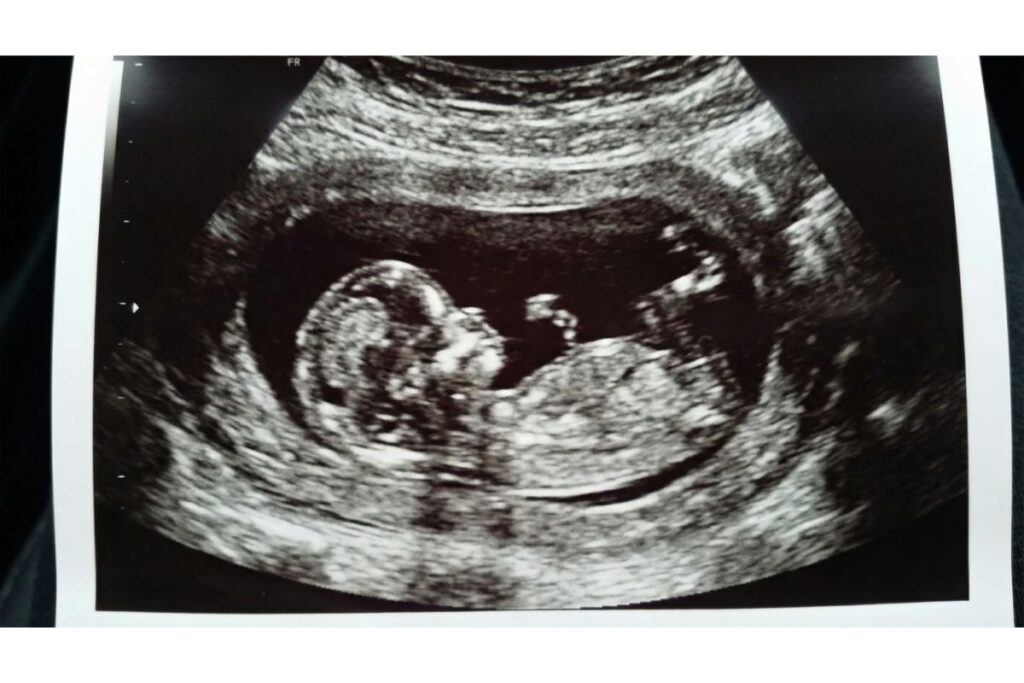

The Nuchal Translucency (NT) scan is typically the first major ultrasound you will encounter. It is a screening test performed in the first trimester.

- Timing: This scan must be done specifically between 11 and 14 weeks of pregnancy. It cannot be done later because the fluid being measured gets absorbed by the baby’s body after 14 weeks, making the results unreliable.

- Purpose: The primary goal is to measure the thickness of the nuchal translucency, which is a fluid-filled space at the back of the baby’s neck. Thicker fluid measurements can indicate a higher risk of chromosomal abnormalities, such as Down syndrome (Trisomy 21), Edwards syndrome, or Patau syndrome.